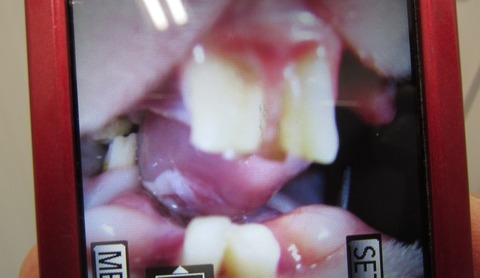

舌の傷もずいぶん良くなってきています。

向かって左側の白くなってるところ

画像で見るとすごく腫れてるように感じますね(;´Д`)